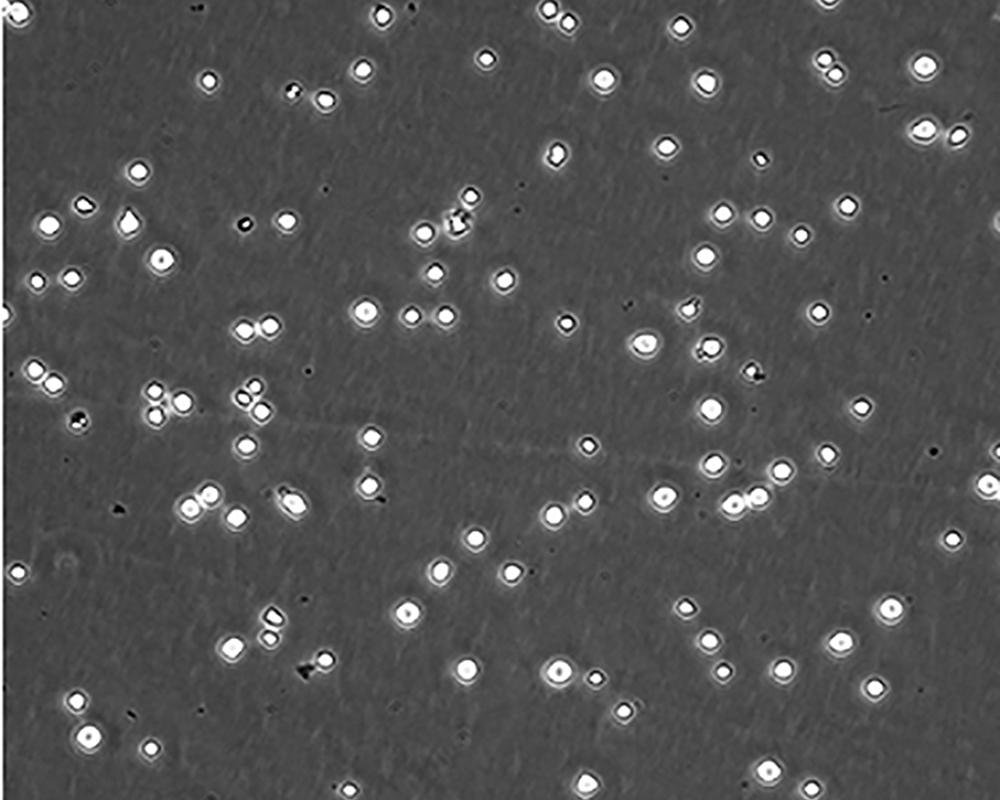

形態(tài)特征 lymphoblast

細(xì)胞描述 CEM/C1是人T細(xì)胞白血病細(xì)胞株CCRF-CEM(見ATCC CCL-119)具有喜樹堿抗性的衍生株。1991年細(xì)胞株選擇并亞克隆了對CPT的抗性。細(xì)胞表現(xiàn)出對CPT類似物水溶性的托泊替康和非水溶性的9-氨基-CPT及10,11-亞甲二氧基-CPT具有交叉抗性。CEM/C1細(xì)胞對CPT的敏感性較母系CEM細(xì)胞低31倍。CEM/C1細(xì)胞表現(xiàn)非典型的多藥抗性和轉(zhuǎn)換拓補(bǔ)異構(gòu)酶I催化活性。對CPT的抗性維持6個月以上。